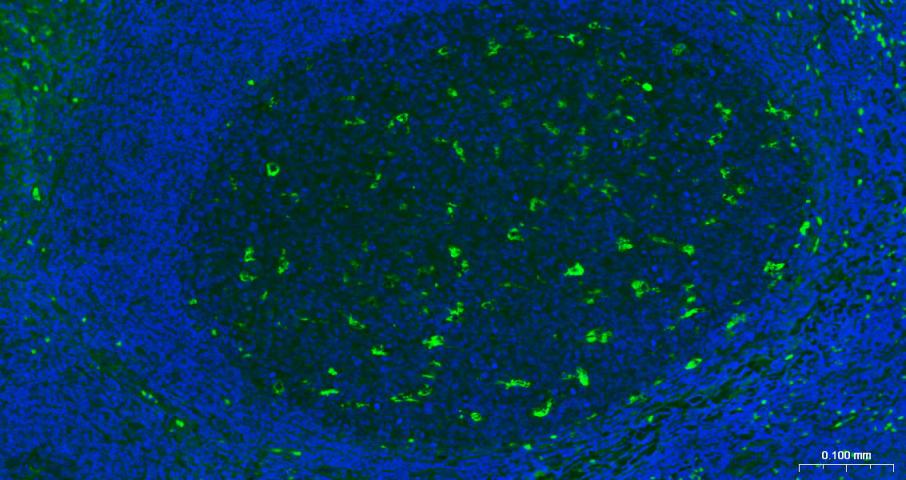

| 英文名称 | CD68 Mouse mAb |

| 中文名称 | CD68单克隆抗体 |

| 产品应用 | IHC-P=1:50-200, IHC-F=1:50-200, IF=1:50-200 Not yet tested in other applications. |

| {IF} | {1:50-200} |

| 组织特异性 | Highly expressed by blood monocytes and tissue macrophages. Also expressed in lymphocytes, fibroblasts and endothelial cells. Expressed in many tumor cell lines which could allow them to attach to selectins on vascular endothelium, facilitating their dissemination to secondary sites. |

| 功能 | Could play a role in phagocytic activities of tissue macrophages, both in intracellular lysosomal metabolism and extracellular cell-cell and cell-pathogen interactions. Binds to tissue- and organ-specific lectins or selectins, allowing homing of macrophage subsets to particular sites. Rapid recirculation of CD68 from endosomes and lysosomes to the plasma membrane may allow macrophages to crawl over selectin-bearing substrates or other cells. |

| 背景资料 | This gene encodes a 110-kD transmembrane glycoprotein that is highly expressed by human monocytes and tissue macrophages. It is a member of the lysosomal/endosomal-associated membrane glycoprotein (LAMP) family. The protein primarily localizes to lysosomes and endosomes with a smaller fraction circulating to the cell surface. It is a type I integral membrane protein with a heavily glycosylated extracellular domain and binds to tissue- and organ-specific lectins or selectins. The protein is also a member of the scavenger receptor family. Scavenger receptors typically function to clear cellular debris, promote phagocytosis, and mediate the recruitment and activation of macrophages. Alternative splicing results in multiple transcripts encoding different isoforms. [provided by RefSeq, Jul 2008] |